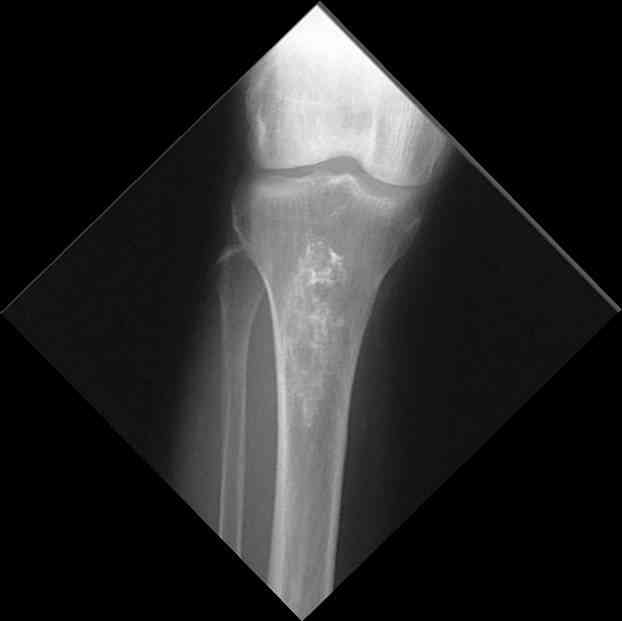

Мужчина, 53 года, жалуется на постоянные ноющие боли в костях голеней, усиливающиеся после ходьбы, боли в коленных суставах. Считает себя больным с 1987 г., когда впервые появились боли в коленных суставах. В 1990 г. выставлен д-з: вторичный ДОА коленных суставов, фиброзная дисплазия костей. После проведенного лечения (НПВП, радоновые ванны, курс введения кислорода в коленные суставы) в течение 5 лет ремиссия. С 1995 г. ежегодные обострения весной и осенью, проявляющиеся болями в коленных суставах, явлениями синовита. Проводилось лечение НПВП, физиопроцедуры, внутрисуставное введение дипроспана с положительным эффектом. С 2004 г. - эффекта от проводимой терапии нет. В 2006 г. впервые по рентгеновским снимкам выставлен д-з: болезнь Альберса-Шенберга. Деформирующий гонартроз справа 2 ст., слева 3 ст. С 2006 г. ездит на лечение в Китай, где проводится лечение радоновыми грязями, массаж с положительным эффектом. Объективно: коленные суставы деформированы, при пальпации б/болезненные. Движения в полном объеме. При ходьбе хромает. Диагноз: болезнь Алберс-Шонберга. Деформирующий гонартроз справа 2 ст., слева 3 ст.Хотелось бы уточнить диагноз и определить тактику дальнейшего лечения. Заранее спасибо.

Представленные Вами данные о пациенте 57 дет с болезнью Альбертс-Шенберга чрезвычайно интересны, но диагноз вызывает большие сомнения. Для мраморной болезни характерно прееобладание склероза, а на представленных рентгенограммах преобладает симметричная дезорганизация архитектоники губчатой кости в эпиметафизарной зоне дистальных отделов бедер и голеней.

Мне кажется, представленные рентгенограммы скорее соответствуют варианту фиброзной дисплазии который был описан М. Campanacci (1976) или

обызвествляющей фиброме H.E.Schlitter (1958).

Уважаемый Константин Иванович! Полностью согласен с проф. Михайловым, данный случай не похож на мраморную болезнь, при которой имеется резкое, строго симметричное и генерализованное уплотнение костной ткани (остеопетроз), и кость оказывается построенной преимущественно из гомогенного компактного костного вещества. Для примера привожу случай из архива нашего института (бедренные, плечевые кости и таз, рис 1,2,3)

Изменения структуры костей у Вашего пациента больше похожи на полиоссальную форму фиброзной дисплазии или болезнь Педжета, возможены также инфаркты костного мозга б.берцовых костей. К сожалению, качество снимка не очень хорошее, непонятно, сохранен ли кортикальный слой б.берцовых костей по передней поверхности.

Не являюсь специалистом по костной патологии, но мне кажется, на ренгенограмме множественные мета-диафизарные образования напоминяющее змееподобных извилистых линии и периостеальные ламинирование очень напоминяет картину остеонекроза (инфаркта) костей, возможно связано с длительным применением стероидов.